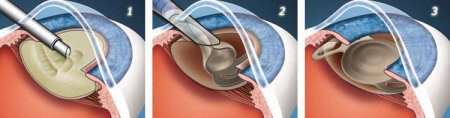

Как проходит операция

- Удаление помутневшего хрусталика;

- Введение ИОЛ;

- Размещение ИОЛ

Суть процесса факоэмульсификации заключается в раздроблении и отсасывание частиц помутневшего хрусталика с помощью ультразвукового зонда. Оперативное вмешательство проходит с применением специальных растворов защищающих другие участки глазного яблока от ультрафиолетового воздействия.

Микроразрез, длиной в 3 мм, способствует быстрому заживлению и снижает риск развития осложнений. Незначительный размер сечения позволяет не прибегать к герметизации шва и наложению швов.

ИОЛ вводят в капсулу, где находился хрусталик с катарактой, через микроразрез, предварительно свернув ее трубочкой. В полости глазного яблока искусственную линзу размещают в соответствии с физиологическими особенностями.